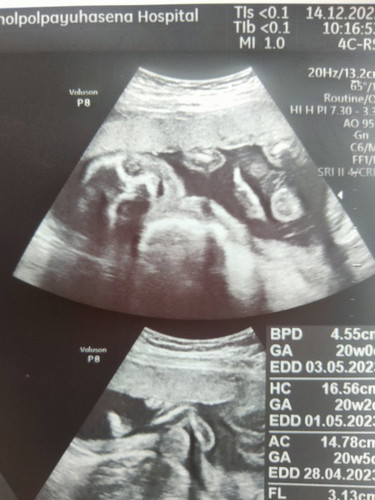

สอบถามแม่ๆหน่อยคะ ไปอัลตร้าซาวด์ มาแล้วหมอให้ใบแบบนี้มา ตรงนี้คือ อวัยวะ ส่วนไหนของลูกน้อย คะ หมอไม่ได้บอกคะ #ขอบคุณสำหรับคำตอบค่ะ

น้องหันมายิ้มให้ด้วย เอ็นดู ตา จมูก ปาก ชัดเจนค่ะ น้ำหนักน้องกี่กรัมคะ อายุครรภ์ห่างกันแค่ 1 วันเอง

ภาพบนเป็นส่วนของใบหน้าค่ะ